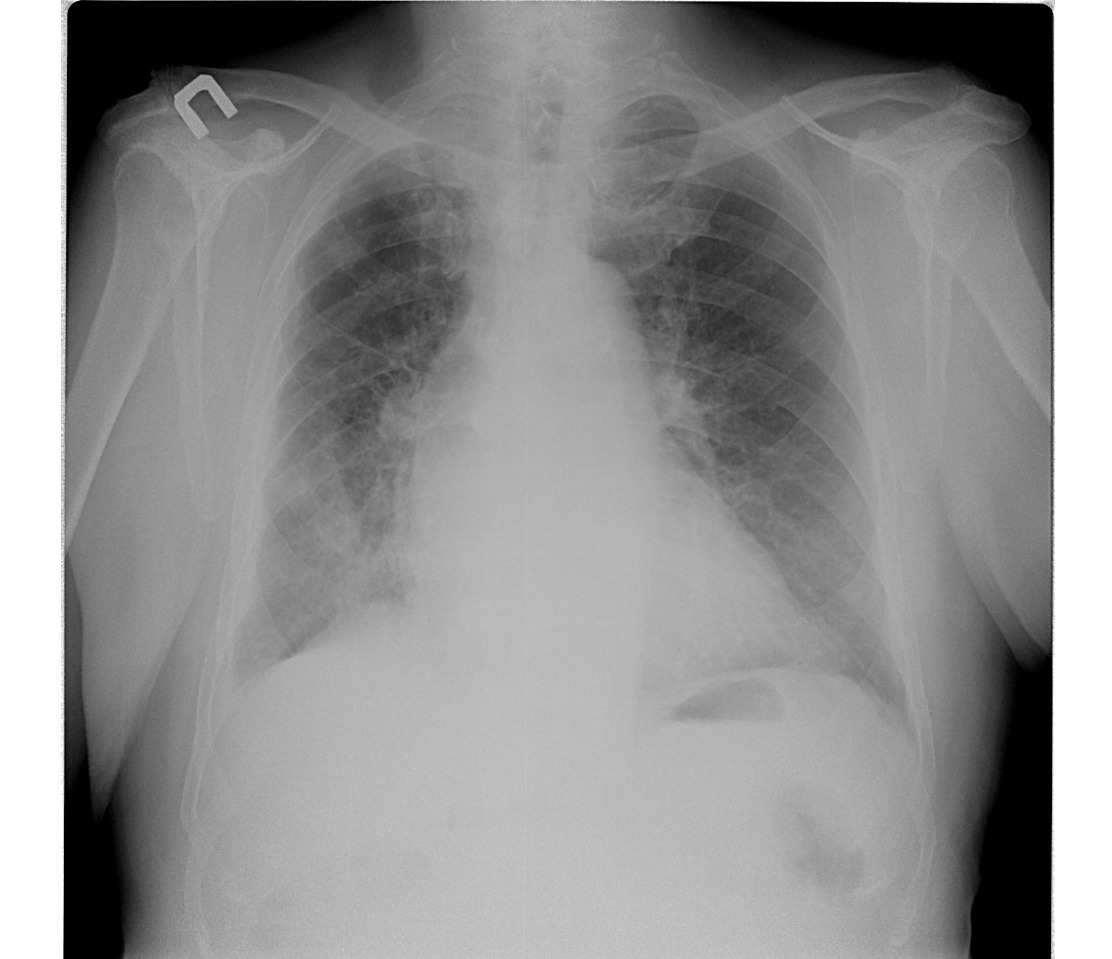

Шварта. Видно на боковом.

она же и на прямом такая обширная что ль?

Эти так называемые дела можно назвать уплотнённой междолевой плеврой.)) Это главная которая. У кардиологических, бывает, плотнеет она.